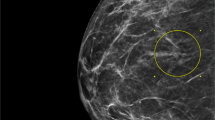

The study was approved the Institutional Review Board of Carolinas Medical Center. Breast core biopsies with a diagnosis of flat epithelial atypia from 1 January 2004 to 15 October 2013 were retrieved from the Anatomic Pathology information system (CoPath). For all core biopsies, the presence and type of co-existing atypical ductal hyperplasia or atypical lobular hyperplasia or carcinoma was recorded. Cases with co-existing atypical ductal hyperplasia or atypical lobular hyperplasia or carcinoma and cases without an excision pathology report in CoPath were excluded from further study. Cases with atypical ductal hyperplasia or atypical lobular hyperplasia, carcinoma in situ, or invasive carcinoma in ipsilateral core biopsies performed concurrently or within 4 months of the core biopsy with flat epithelial atypia were also excluded. All study cases were reviewed by dedicated breast pathologists (CAL and BCC) to confirm the diagnosis of pure flat epithelial atypia using WHO criteria. These criteria include enlarged terminal duct lobular units, often with 3–5 cell layers, with proliferation of cells showing low-grade monomorphic cytology, increased nuclear/cytoplasmic ratios, and loss of polarity (Figure 1). Multiple levels were examined in all cases. From 2009 through completion of the study period, a cutting protocol obtaining six (6) H&E levels ∼150–250 microns apart were routinely examined for each stereotactic core biopsy. Before that change, the diagnostic pathologist requested additional levels (usually three) in all cases in which a ‘stand alone’ diagnosis of flat epithelial atypia was entertained. At least six levels were examined in the final study group (73 core biopsies with flat epithelial atypia alone).